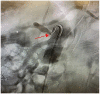

Median arcuate ligament syndrome (MALS), also known as celiac artery compression syndrome, is a rare gastrointestinal condition with an estimated incidence of 2 per 100 000 population. Predominantly in female patients, this syndrome is characterized by the compression of the celiac artery at its origin from the aorta by the median arcuate ligament, which at the same time is entrapping the celiac plexus, causing upper abdominal pain, notably postprandial pain, as well as nausea, vomiting, food aversion, and weight loss. We present a case of abdominal pain secondary to MALS that was appropriately diagnosed after requiring narcotic medication, which responded to surgical therapy.